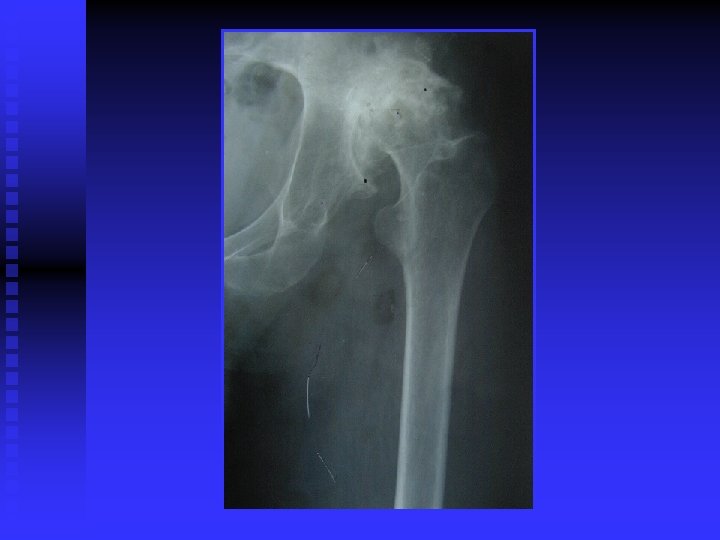

OA RÖNTGEN BULGULARI n Eklem aralığında daralma (kıkırdak incelmiş) n Eklem aralığının kalmaması (kıkırdak bitmiş) n Yük binen yerlerde kistler n Yük binmeyen yerlerde osteofitler

SEKONDER OA Post travmatik n Konjenital n Lokalize n • Kalça hastalığı (perthes, GKD ) Mekanik ve lokal faktörler ( obesite ) Aks bozuklukları (valgus-varus ) n Sistemik • Metabolik hastalıklar Romatoid artrit Endokrin hastalık (akromegali ) • •